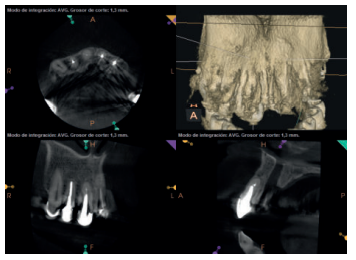

Para confirmar el origen endodóntico y el tamaño de las lesiones se realizaron exploraciones tomográficas con espesor de corte de 75 micras mediante CBCT CS8100 (Carestream Dental® ) en las que se evidenciaron lesiones periapicales radiolúcidas a nivel de 12, 11, 21 (con afectación bicortical), 25 y raíces vestibulares de 26 (Figuras 4 a 8).